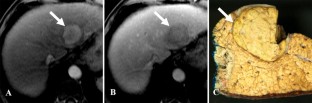

Fig. 1